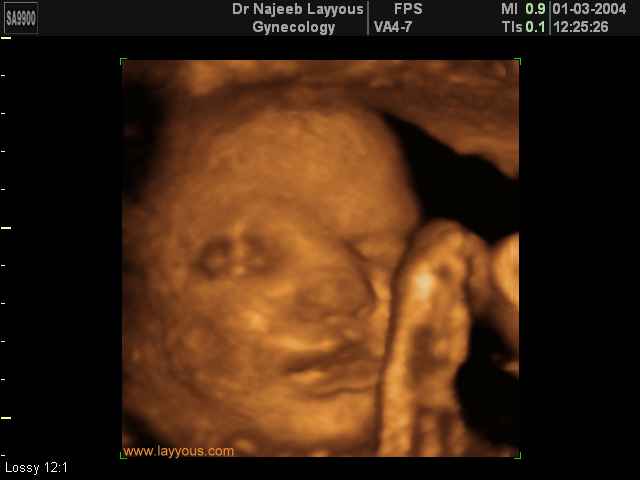

صور لوجه الجنين بجهاز الالتراساوند ثلاثي الأبعاد | الدكتور نجيب ليوس

صور لوجه الجنين بجهاز الموجات فوق صوتية ثلاثي الأبعاد